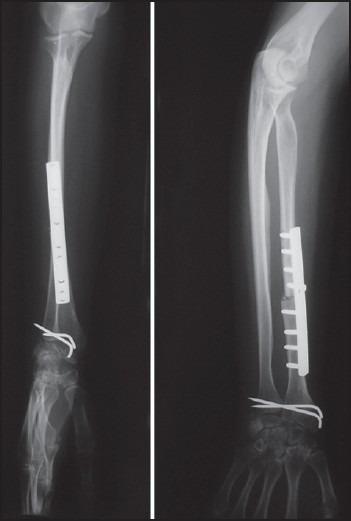

Although giant cell tumor (GCT) is considered to be a primary benign bone tumor, its aggressive behavior makes its diagnosis and treatment, difficult and challenging. This is especially true in distal radius where GCT appears to be more aggressive and difficult to control locally. We report our clinical outcome of en-block resection and reconstruction with non-vascularized fibular autograft in 15 patients with distal radius GCT.

We retrospectively reviewed 15 patients with GCT (Grade 2 and 3) of distal radius who were treated with en-block resection and non-vascularized fibular autograft. Five of 15 were recurrent GCT treated initially with extended curettage; local adjuvant therapy and filling the cavity with cement or bone graft. We followed the patients for mean 7.2 years post operation (range: 4-11 years). Patients were evaluated post operation with clinical examination, plain radiography of distal radius and chest X-ray and/or computed tomography scan. Furthermore pain, function, range of motion and grip strength of the affected limb were evaluated and mMayo wrist score was assessed.

A total of 11 patients were women and 4 were men. Mean age of patients was 29 years (range: 19-48). We had no lung metastasis and bony recurrence occurred in one patient (6.6%). Nearly 53.3% of patients had excellent or good functional wrist score, 80% of the patients were free of pain or had only occasional pain and 80% of patients returned to work. Mean range of motion of the wrist was 77° of flexion-extension and mean grip strength was 70% of the normal hand.

En-block resection of distal radius GCT and reconstruction with non-vascularized fibular autograft is an effective technique for treatment in local control of the tumor and preserving function of the limb.